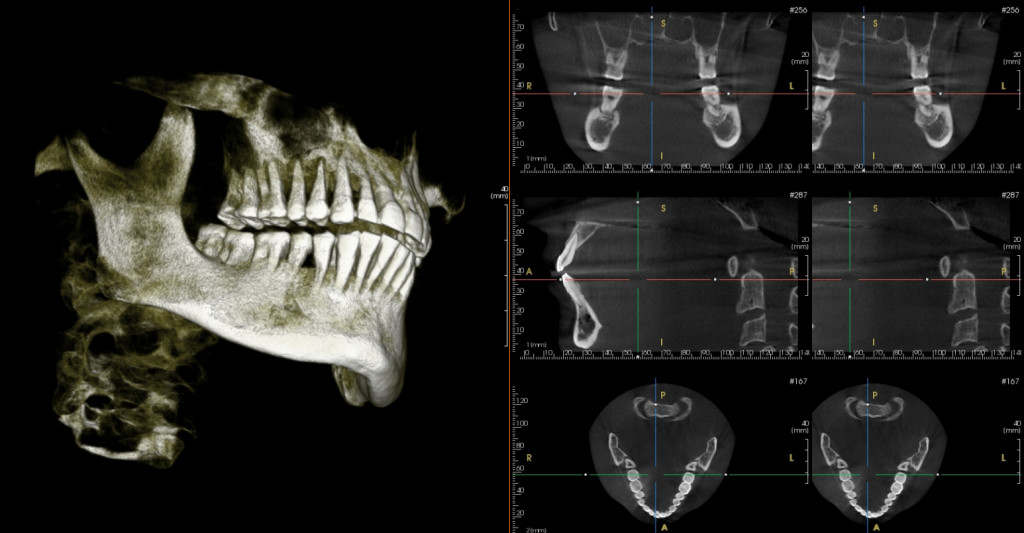

TOMOGRAFÍA 3D

Este estudio de Radiología dental es lo más moderno en diagnóstico, es realizada por medio de un tomógrafo, al momento el único en Machala, permite ver en todos los planos del espacio cualquier estructura dental y ósea de cabeza y cuello, incluso se puede manipular las imágenes para cambiar contrastes, acercamientos y giros en todos los planos del espacio. Estos estudios con recibidos por el profesional o paciente por el moderno sistema Drop-Box, que consiste, en que el estudio siempre estará en un nube virtual, pudiendo acceder a estos en cualquier lugar del mundo.